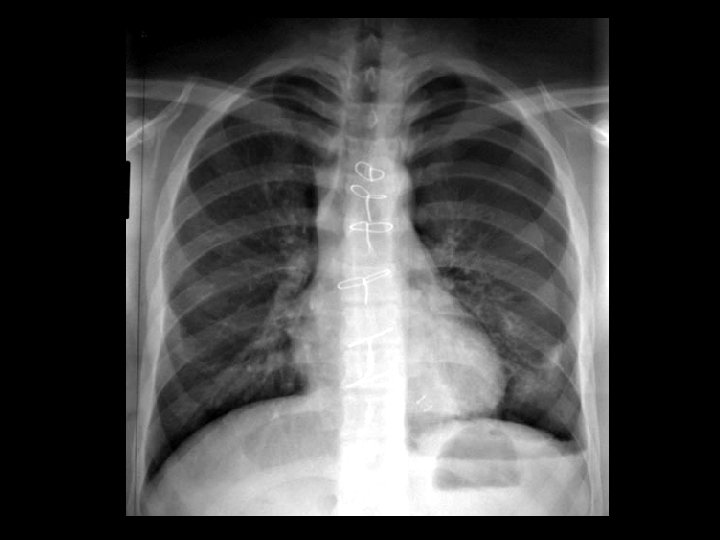

Cryptogenic organizing pneumonia (COP) • Findings: – patchy air-space consolidation in a predominantly peripheral and subpleural distribution • Unknown cause, assoc/w – connective tissue d/o – cocaine/drugs – HIV – MDS • ddx: – Chronic esosinophilic pneumonia – diffuse alveolar hemorrhage